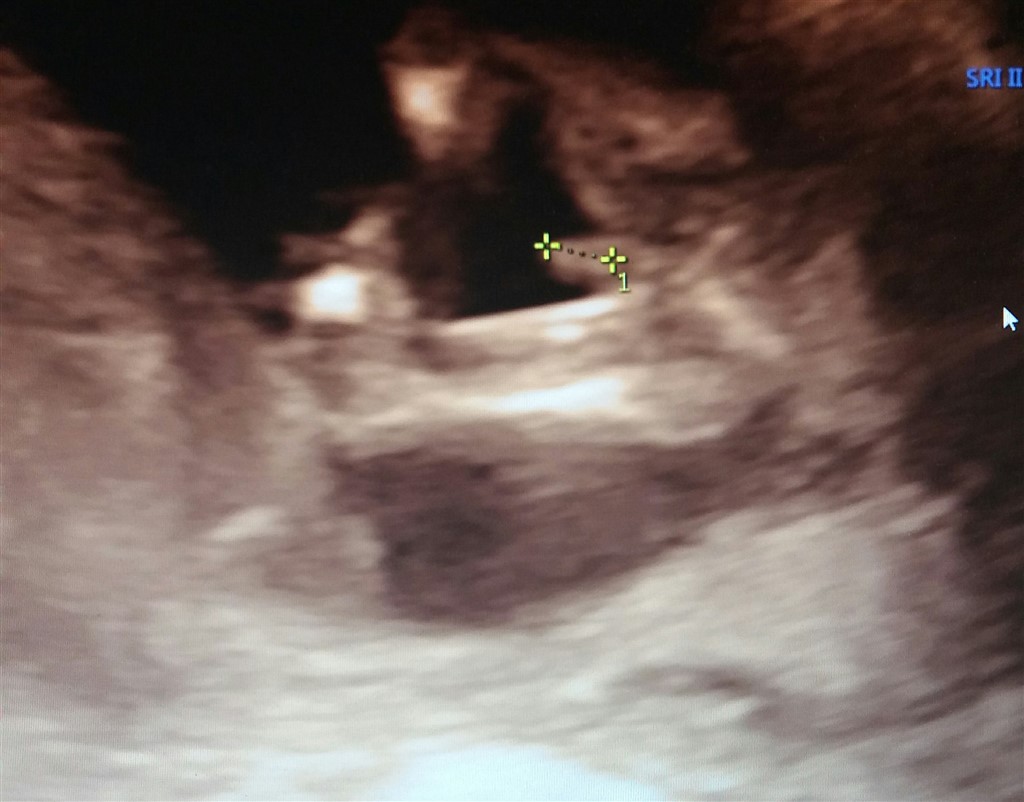

Dette skulle være en dreng. Men har endnu ikke født

Vedhæftede fotos (klik for at se i fuld størrelse)